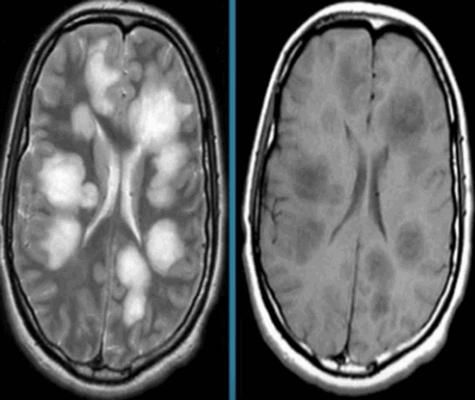

| Признаки РС на МРТ | Норма и очаги рассеянного склероза на МРТ снимках |

Признаками рассеянного склероза головного и спинного мозга на МРТ изображениях будут:

- слабовыраженные очаговые изменения, повышение сигнала Т2;

- типичное вовлечение спинного мозга;

- распространенность не более двух сегментов;

- поражения латеральных или задних столбов белого вещества с возможным вовлечением центральных отделов;

- в острой фазе утолщение спинного мозга;

- в хронической фазе слияний очагов;

- атрофические изменения в мозге - заместительная гидроцефалия.